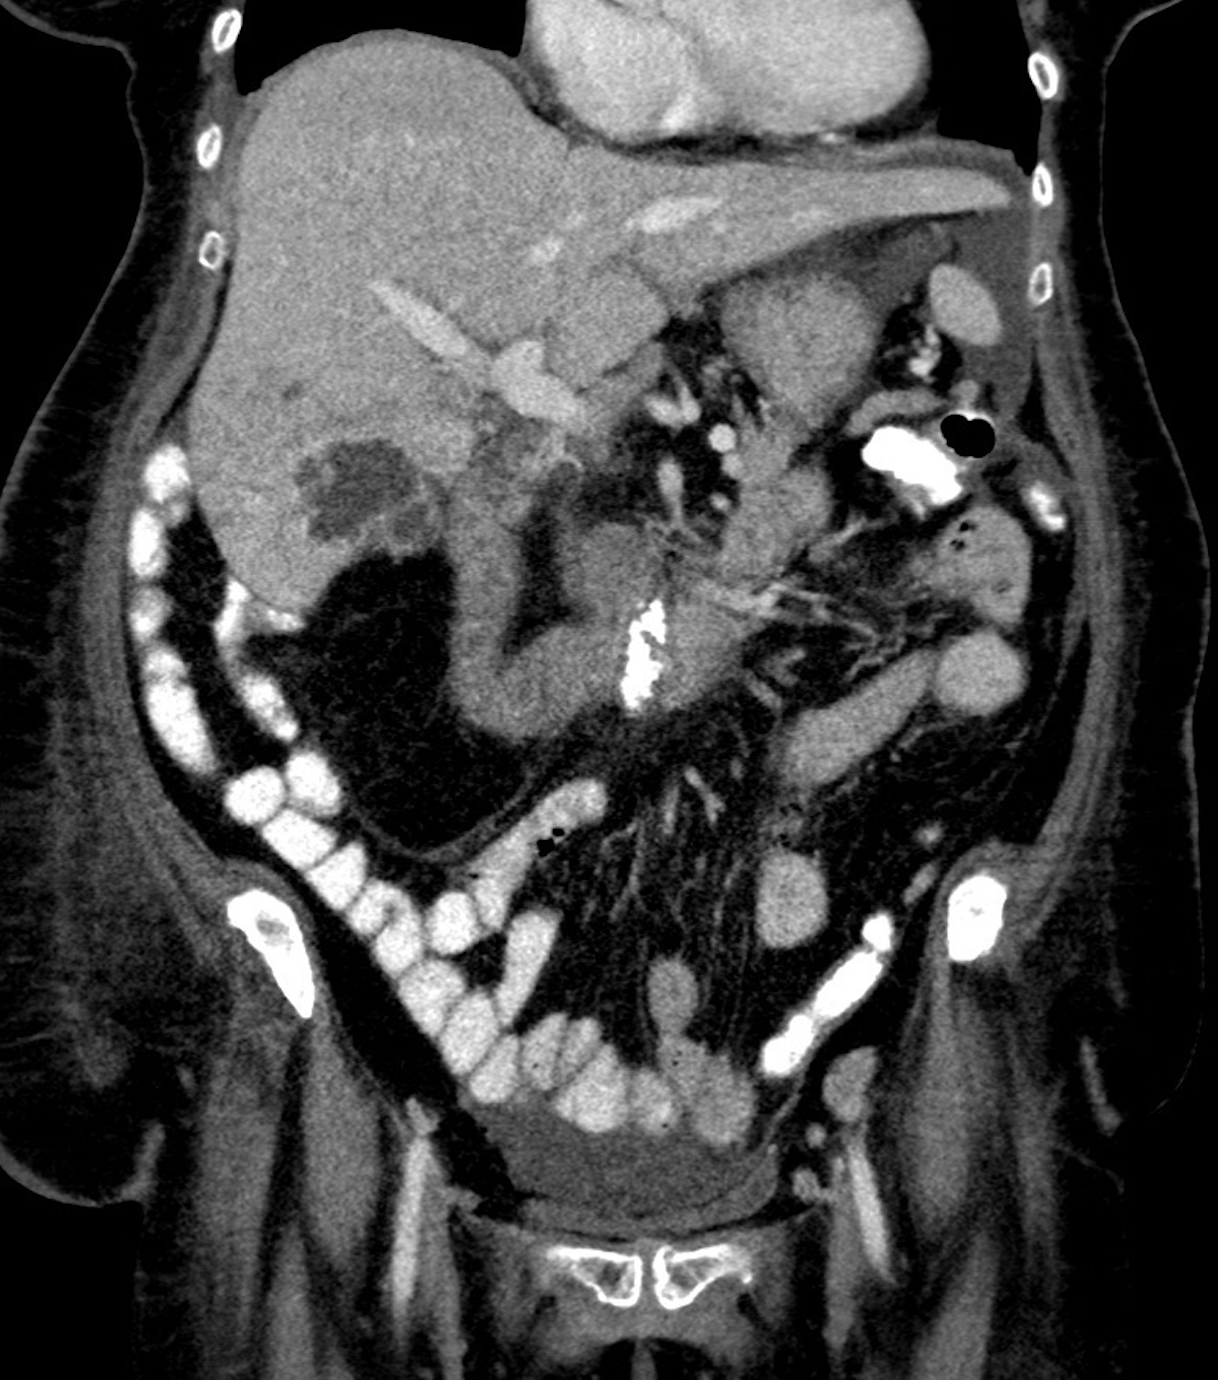

metastase hepatica na tc

TC axial aprimorada pelo contraste demonstra múltiplas lesões hepáticas hipodensas de tamanhos variados com borda periférica (aparência targetoid